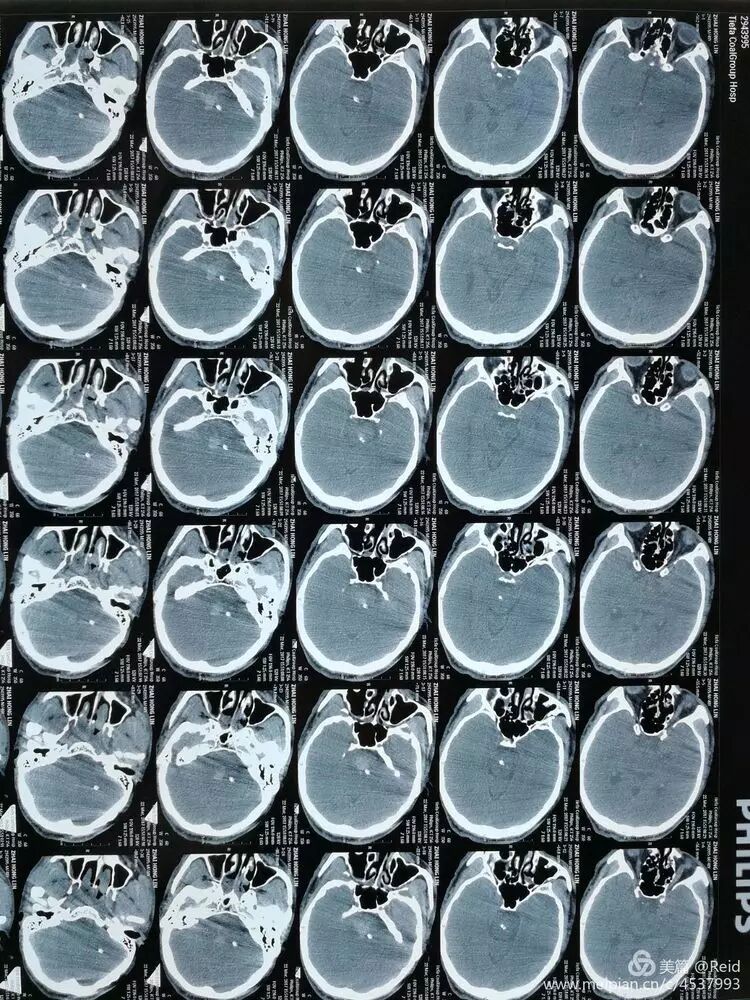

男患,50岁,突发意识障碍2小时入院。既往有高血压病史数年,治疗不规范。入院时病人深昏迷,GCS=1+1+2,双瞳孔2mm,四肢无活动,生命指标正常。入院后家属选择保守治疗。入院24小时后呼吸减慢,<10次/分,浅表,给予呼吸机辅助呼吸。

保守治疗72小时后,病情无明显改善,家属决定尝试外科手术干预,谨慎沟通后,以移动呼吸机辅助下,经CT引导精确定位置管手术。